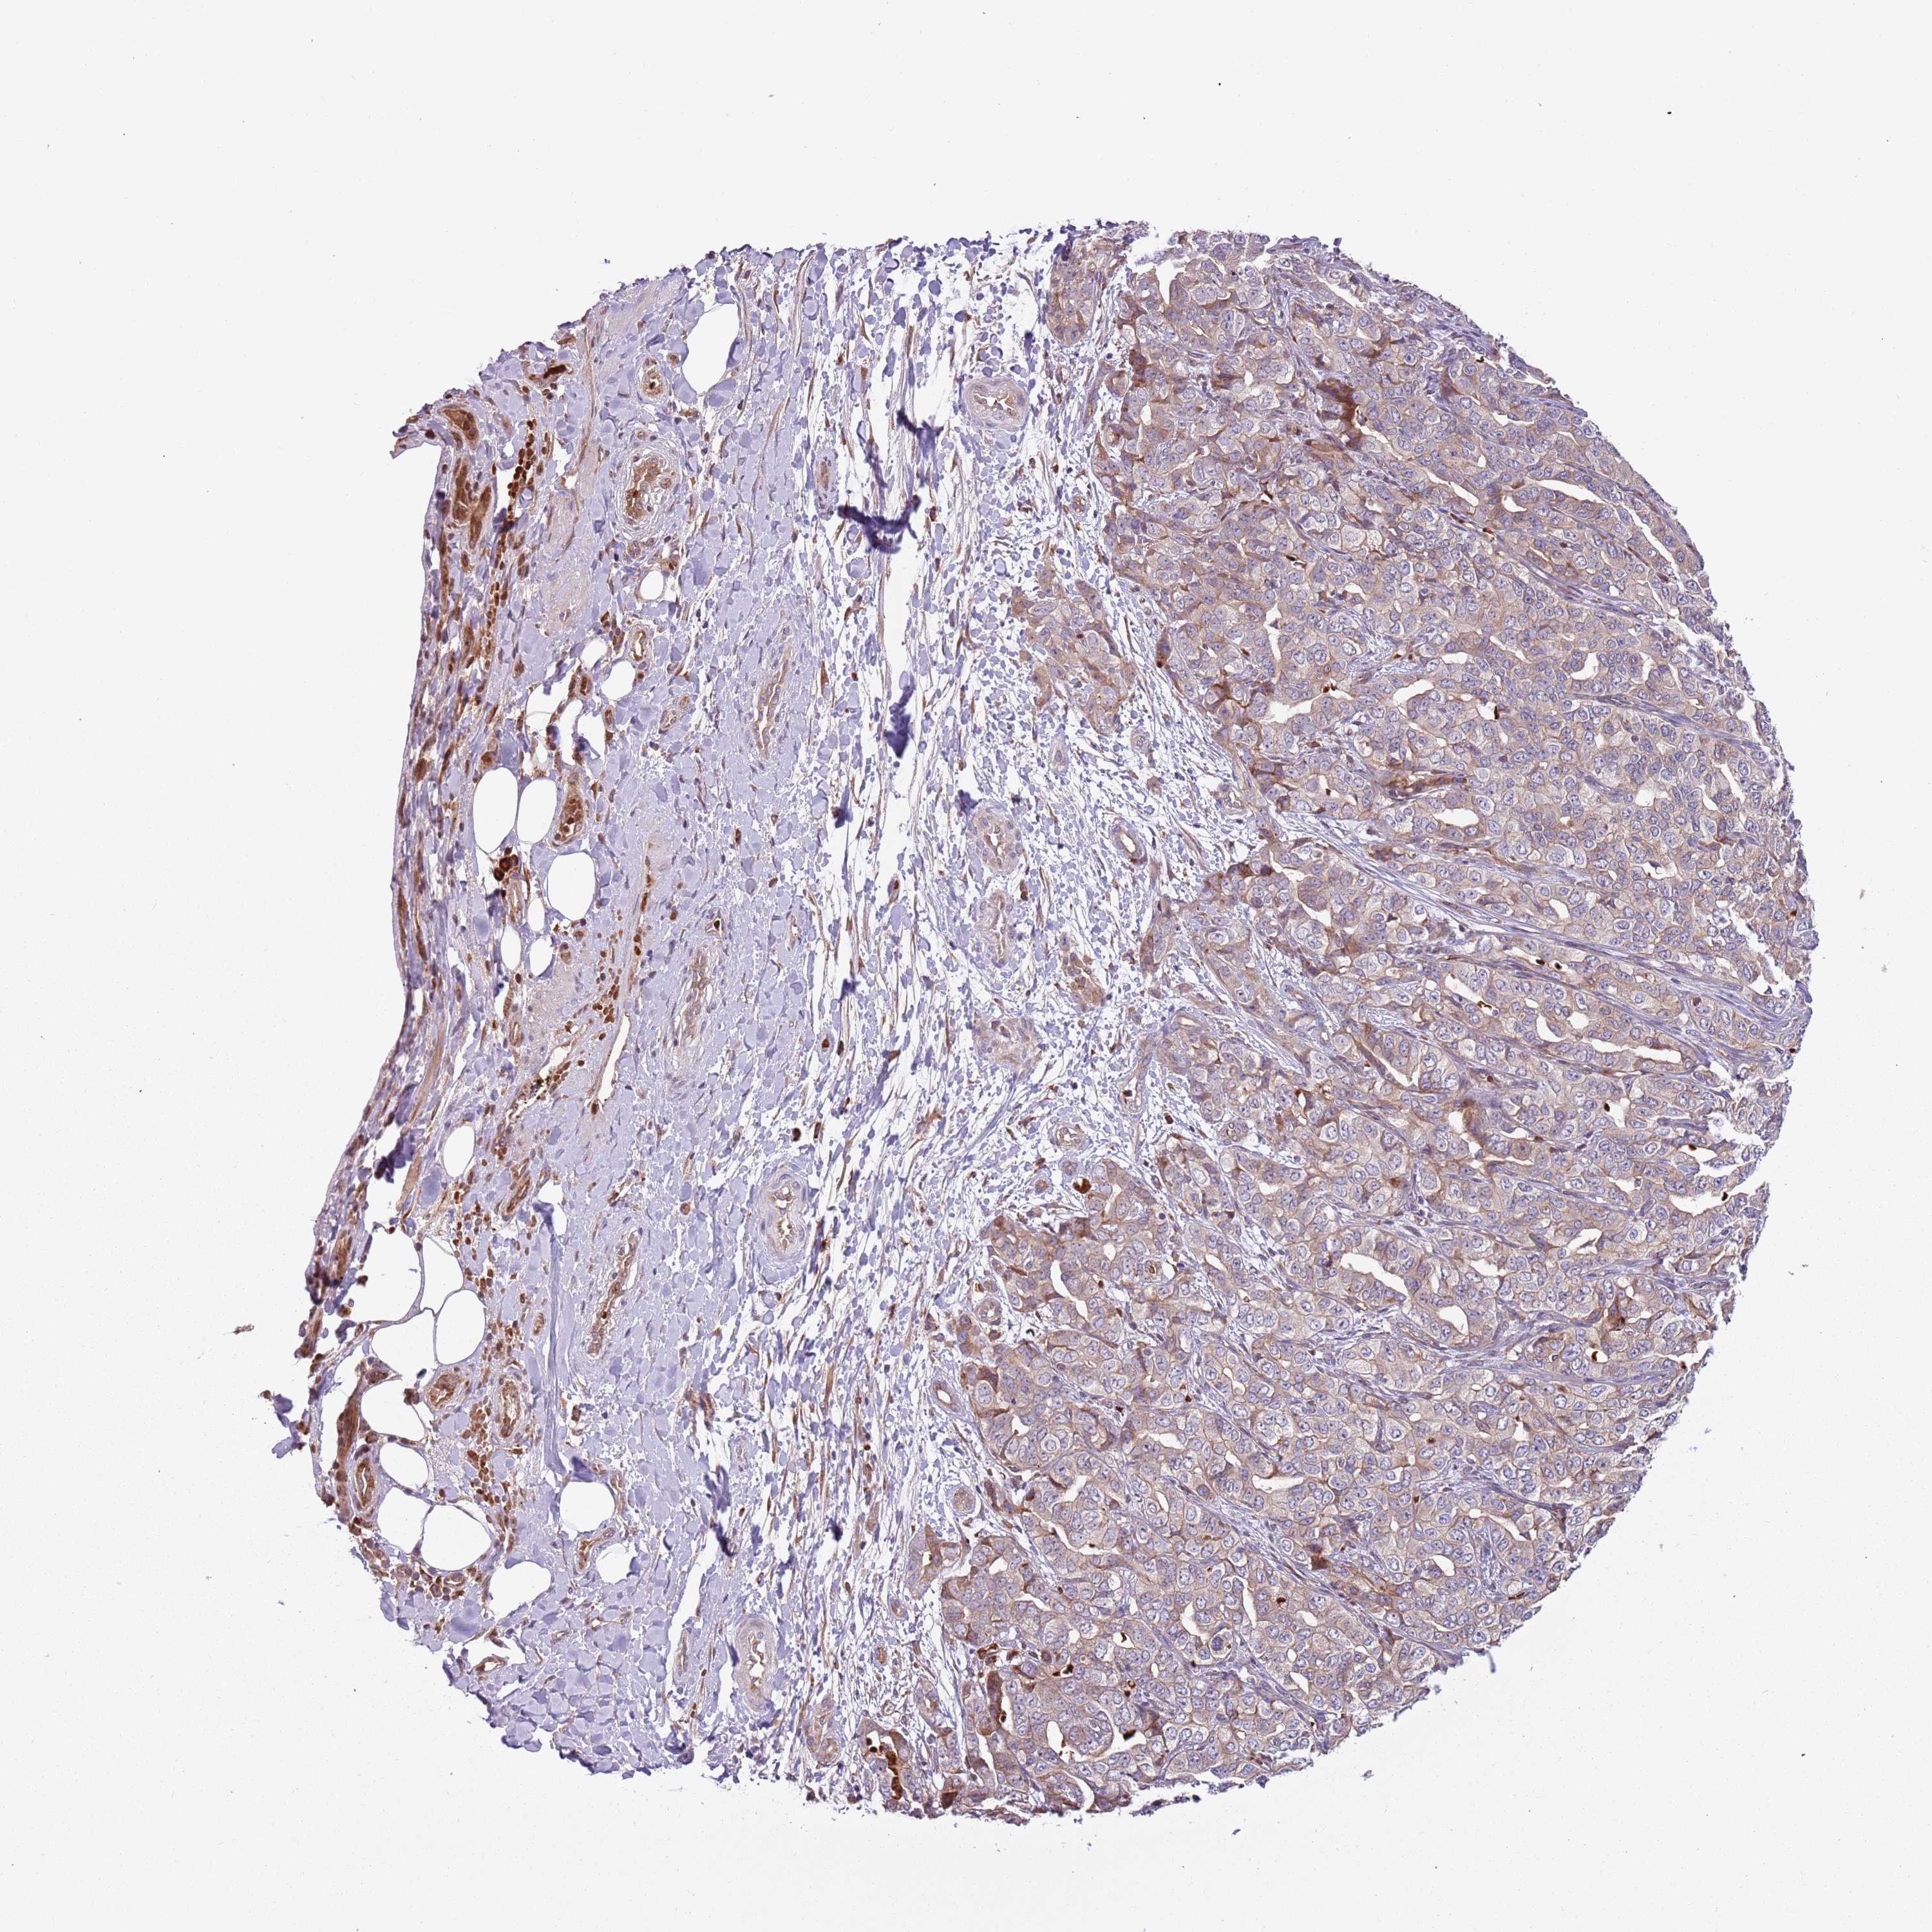

LIVER CANCER - Protein expressioni

A mouse-over function shows sample information and annotation data. Click on an image to view it in a full screen mode. Samples can be filtered based on level of antibody staining by selecting one or several of the following categories: high, medium, low and not detected. The assay and annotation is described here.

Note that samples used for immunohistochemistry by the Human Protein Atlas do not correspond to samples in the TCGA dataset.

Antibody stainingi

Antibody staining in the annotated cell types in the current human tissue is reported as not detected, low, medium, or high, based on conventional immunohistochemistry profiling in selected tissues. This score is based on the combination of the staining intensity and fraction of stained cells.

Each image is clickable and will lead to virtual microscopy that enables deeper exploration of all samples and also displays staining intensity scores, fraction scores and subcellular localization as well as patient and tissue information for each sample.

Antibody HPA040401

Antibody HPA043921

Staining

High

Medium

Low

Not detected

Intensity

Strong

Moderate

Weak

Negative

Quantity

>75%

75%-25%

<25%

None

Location

Nuclear

Cytoplasmic/membranous

Cytoplasmic/membranous,nuclear

Cholangiocarcinoma

Carcinoma, Hepatocellular, NOS